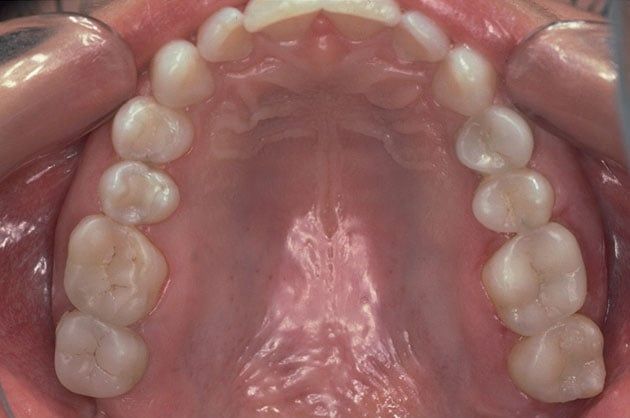

Composite fillings are today's modern filling choice. They are made to match your tooth's natural color to make them virtually invisible to notice and are placed onto the tooth by bonding the filling material to the tooth so they do not have the unlikely chance of falling off. Many patients choose to replace their old silver and gold fillings with composite fillings.

White fillings are made from a high-strength composite resin that can be easily color-matched to your natural tooth making it nearly invisible to you and anyone else. Unlike silver and gold fillings, composite tooth-colored fillings actually bond to the tooth which means they support the surrounding tooth structure, which helps to prevent breakage and insulate the tooth from excessive temperature changes. You are much less likely to have a composite filling fall out which is a common issue with metal fillings.